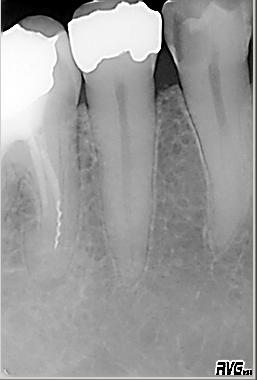

Röntgenologischer Ausgangsbefund im Januar 1993 bei Zahn 34 unmittelbar vor ZE Neuversorgung. Als sicheres Zeichen für das Vorhandensein zweier Kanalsysteme ist das scheinbar abrupte Verschwinden des im koronalen Wurzeldrittels deutlich sichtbaren „Pulpastumpfes“ zu werten